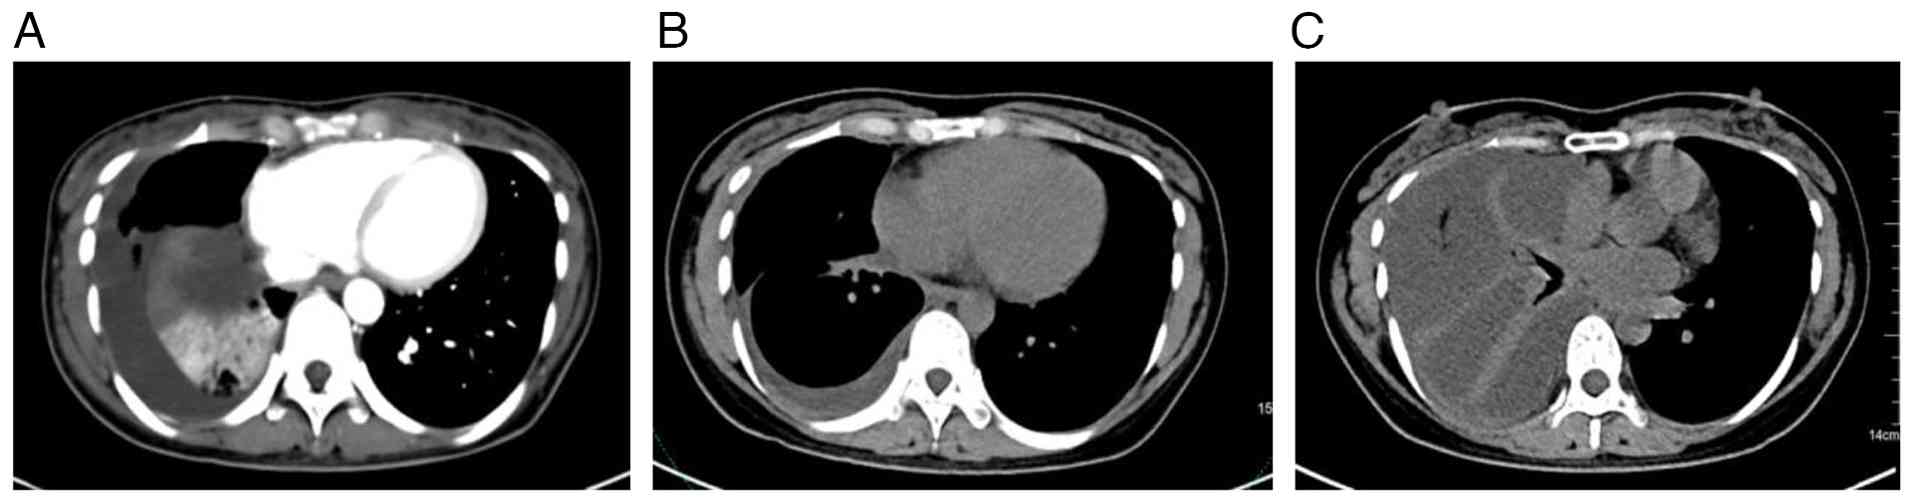

In August 2023, a 36-year-old female patient presented to a general physician in The People's Hospital of Tiantai County (Taizhou, China) with a cough and asthma that had persisted for >1 month. A lung CT scan (Fig. 1A) revealed a mass near the hilum of the right lung, suggesting a malignant tumor with partial atelectasis of the right lower lung. A thoracic puncture and drainage were performed. Cytopathology of centrifugal smears from the right pleural effusion and from bronchoalveolar lavage fluid-a diagnostic technique that analyzes fluid retrieved from the alveolar surface-revealed red blood cells, inflammatory cells and heterogeneous cell clusters, findings diagnostic for adenocarcinoma (Fig. 2). Genetic analysis (Data S1) detected an EGFR exon 19 deletion [c.22402254del; p.L747T751del; variant allele frequency (VAF)=8.49%] and an exon 20 T790M mutation (c.2369C>T; p.T790M; VAF=10.53%). Following the Chinese Society of Clinical Oncology and National Comprehensive Cancer Network guidelines for lung cancer (7,8), the patient was treated with furmonertinib (80 mg once daily in the morning), a third-generation targeted antitumor therapy.

Imaging examination results of the

disease course. (A) Baseline CT (August 2023): Mass shadow at hilum

of lung, atelectasis of lower lobe of right lung, moderate effusion

in right chest cavity. (B) After 8 months CT (April 2024): The mass

shadow near the hilum of the right lung, the focus was markedly

smaller compared with that at baseline. The multiple small nodules

in the right lung were smaller compared with that at baseline and

the inflammation of both lungs was basically absorbed. The right

pleural thickening, pleural effusion, markedly improved compared

with that at baseline. (C) CT at 1 year later (August 2024):

Atelectasis is progressing and there is a lot of effusion in the

right chest. The right lung is not fully inflated and the right

lung is newly inflamed.

Figure 1.

Imaging examination results of the disease course. (A) Baseline CT (August 2023): Mass shadow at hilum of lung, atelectasis of lower lobe of right lung, moderate effusion in right chest cavity. (B) After 8 months CT (April 2024): The mass shadow near the hilum of the right lung, the focus was markedly smaller compared with that at baseline. The multiple small nodules in the right lung were smaller compared with that at baseline and the inflammation of both lungs was basically absorbed. The right pleural thickening, pleural effusion, markedly improved compared with that at baseline. (C) CT at 1 year later (August 2024): Atelectasis is progressing and there is a lot of effusion in the right chest. The right lung is not fully inflated and the right lung is newly inflamed.

After 8 months of furmonertinib treatment (April 2024), a CT scan of the upper abdomen and pelvic cavity (Fig. 1B) indicated that the mass near the hilum of the right lung was markedly smaller compared with that at baseline, and the enlarged lymph nodes in the mediastinum were no longer detectable. Furthermore, the multiple small nodules in the right lung were reduced in size and the inflammation in both lungs had resolved. There was also notable improvement in the right lung cancer lymphadenitis, right pleural thickening and pleural effusion.

Asthma symptoms recurred 1 year after the first onset of illness (August 2024). Thin-layer CT and three-dimensional lung imaging (Fig. 1C) detected progressive atelectasis and a considerable right chest effusion. The right lung was not fully inflated and new inflammation was noted. Pleural fluid smears indicated cancer cells. Genetic analysis of the pleural effusion exhibited an EGFR exon 19 deletion and the exon 20 T790M missense mutation. The patient returned for a follow-up breast examination two months later, in August 2024. A breast color Doppler ultrasonography (August 2024) detected a solid mass of 2.25×1.12 cm in the upper quadrant of the right breast. The mass had blurred edges and was classified as BI-RADS category 5 (Fig. 3B). A physical examination indicated that the mass was hard and had poor mobility. After the patient's first diagnosis, follow-up was conducted every 2–3 months, with the last follow-up in February 2024. No other abnormalities were found during the follow-up. Therefore, based on the patient's medical history, recurrence of metastatic cancer after local resection is considered.